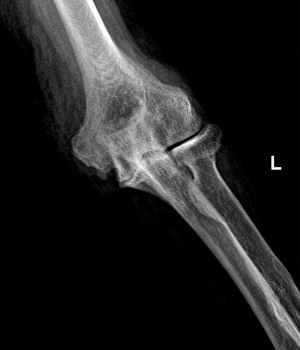

End-Stage Osteoarthritis of the Elbow